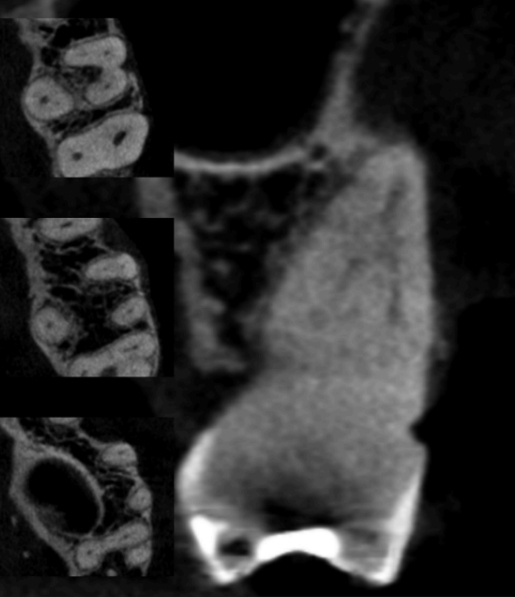

Рисунок 5 — Тип VI (24,8%)

Рисунки 4–6 представляют корональные и аксиальные срезы КЛКТ для трех наиболее часто встречающихся типов анатомических конфигураций.